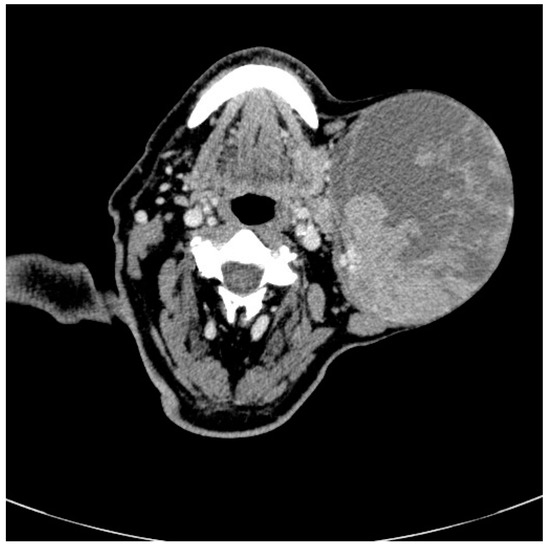

Contrast enhanced computed tomography (Figure 2) revealed a heterogeneous solid cystic lesion measuring 96 mm/102 mm/136 mm, with moderate enhancement within the superficial lobe of the left parotid gland and extension toward the left supraclavicular fossa. The tumor was well defined, with no muscular infiltration or calcifications and the cystic component was displayed as intralesional lower attenuation. The most likely imaging diagnosis was of benign left parotid gland tumor, most probably Warthin’s tumor.

Figure 2.

Radiographic features of Warthin tumor: Axial non-enhanced computed tomography images in bone window show a nodular lesion (see arrow) in the left parotid gland involving the superficial lobe, with dimensions of 15 cm/13 cm.